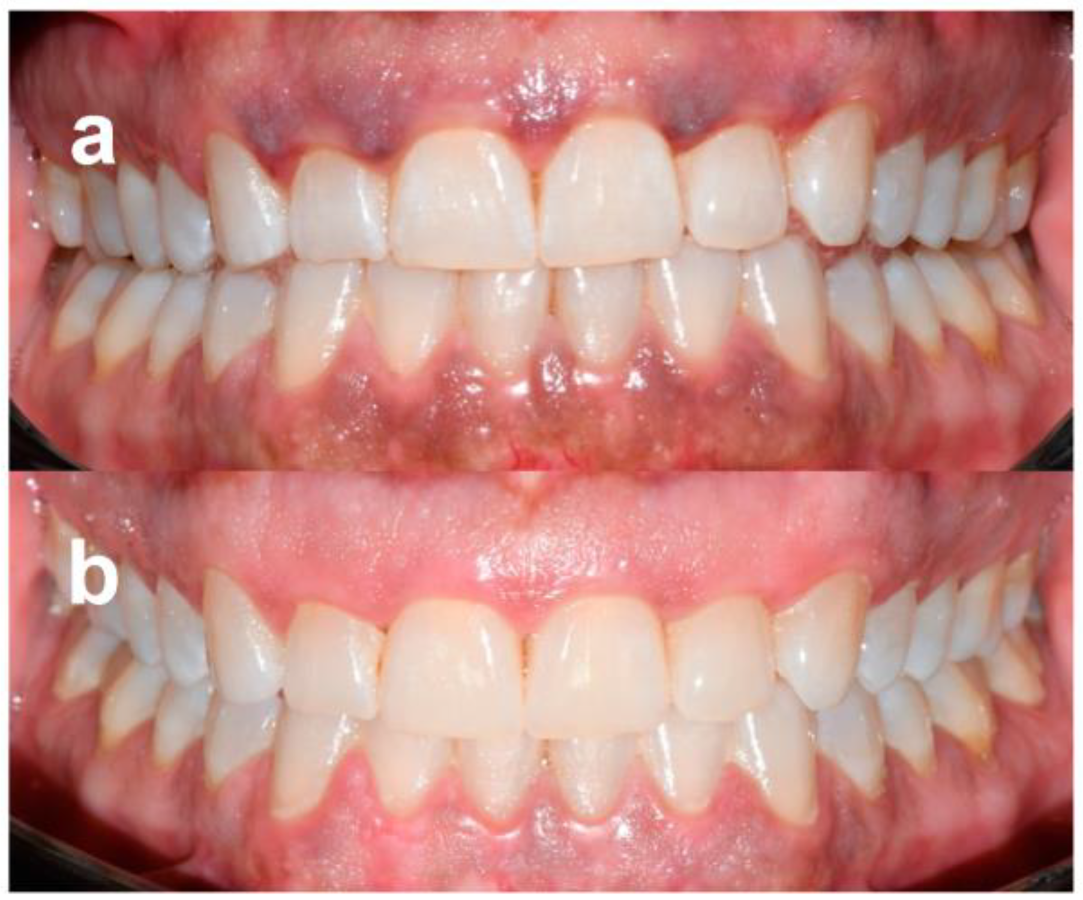

- Score 0: no clinical pigmentation (pink-colored gingiva);

- Score 1: mild clinical pigmentation (mild light brown color);

- Score 2: moderate clinical pigmentation (medium brown or mixed pink and brown);

- Score 3: heavy clinical pigmentation (deep brown or bluish-black color).

- Score 0: no pigmentation;

- Score 1: solitary unit(s) of pigmentation in the papillary gingiva without extension between neighboring solitary units;

- Score 2: formation of continuous ribbon extending from neighboring solitary units.

| Recurrence at 1 year of follow up | NO | NO | NO | NO | NO | NO | NO | NO | NO | NO |